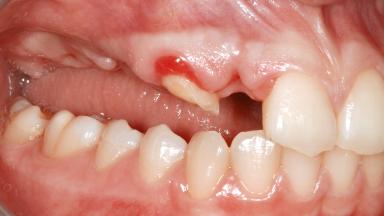

It is well known to clinicians that any removal of teeth will, over time, cause the dimensions of the alveolar ridge to be reduced by resorption of the bundle bone and by changes related to external modeling. This development is particularly evident in the crestal region with its thin buccal bone that consists of bundle bone almost entirely. The facial bone will rapidly resorb as blood supply from the periodontal ligament gets disrupted (Araújo and Lindhe 2005). There is no reason why traumatic tooth loss should not have the same consequences. It takes more than achieving implant osseointegration for a treatment outcome to be considered successful. No deficiency of bone or soft tissue is acceptable when an ideal esthetic outcome is the goal. Several articles (Sanz and coworkers 2011; Vignoletti and coworkers 2011) have reported on techniques of improving the alveolar ridge for implant treatment, notably focusing on protecting tissues from resorption.

| Infection at Implant Site | None | Chronic | Acute |

| Soft Tissue Anatomy | Intact | Defective | |